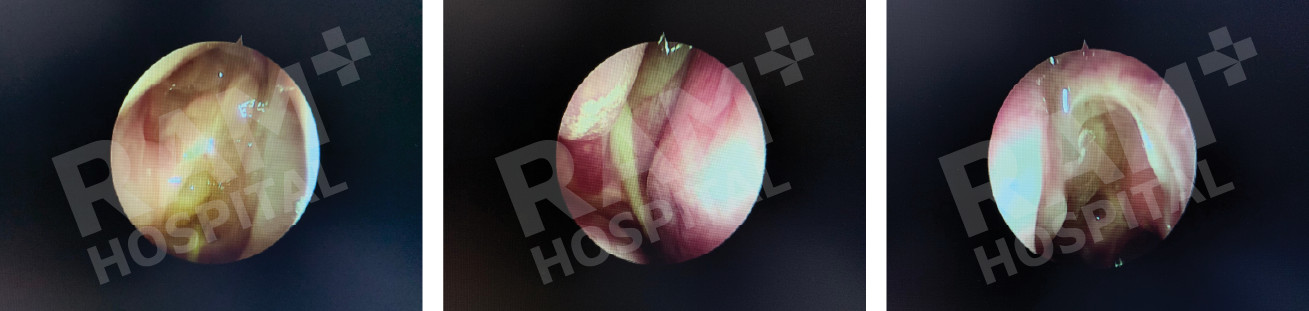

3. 耳部相关手术

内镜下球囊咽鼓管扩张手术

内镜下鼓膜穿孔修补手术

中耳手术内镜辅助 术中内镜探查乳突气房及听小骨,提升手术精度。

脑脊液耳漏修补术

Source: Photo courtesy of Dr. Puripan Aramawattanapong, Ear, Nose, and Throat Specialist